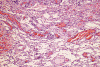

Panel A, B and F are taken from the dermal-epidermal junction. Panel B, C, D, and E are taken from the same area. Panel F, G, H, and I are taken from the same area

The tumor appears to be centered on the dermis and does not involve breast parenchyma in the sections examined A (not shown). On low-magnification (Panel A, B and F), the lesional tissue is a highly cellular and vascular tumor in the dermis. The large areas of hemorrhage ("blood-lake") and dilated vascular channels (Panel A, and F) probably correspond to the "red nodules and yellow patches" on physical examination. Although the tumor extends deeply into the subcutaneous tissue (not shown here), there is no evidence of invasion in to the epidermal layer (Panel A, B and F). The histology of this tumor varies in different areas. In some areas, it appears as a densely packed spindle cell tumor with exuberant and irregular and anastomosing vascular channels (Panel B, C, and D). The endothelial cells protrudes into the vascular channels and had enlarged, hyperchromatic nuclei with  prominent nucleli. In another area, the lesion contains numerous ectactic and anastomosing vascular channels (Panel F, G, H, and I). Pleomorphic changes are also prominent in the vascular cells in these areas. On immunohistochemistry, the tumor cells are immunoreactive for CD31, CD34 (not shown).